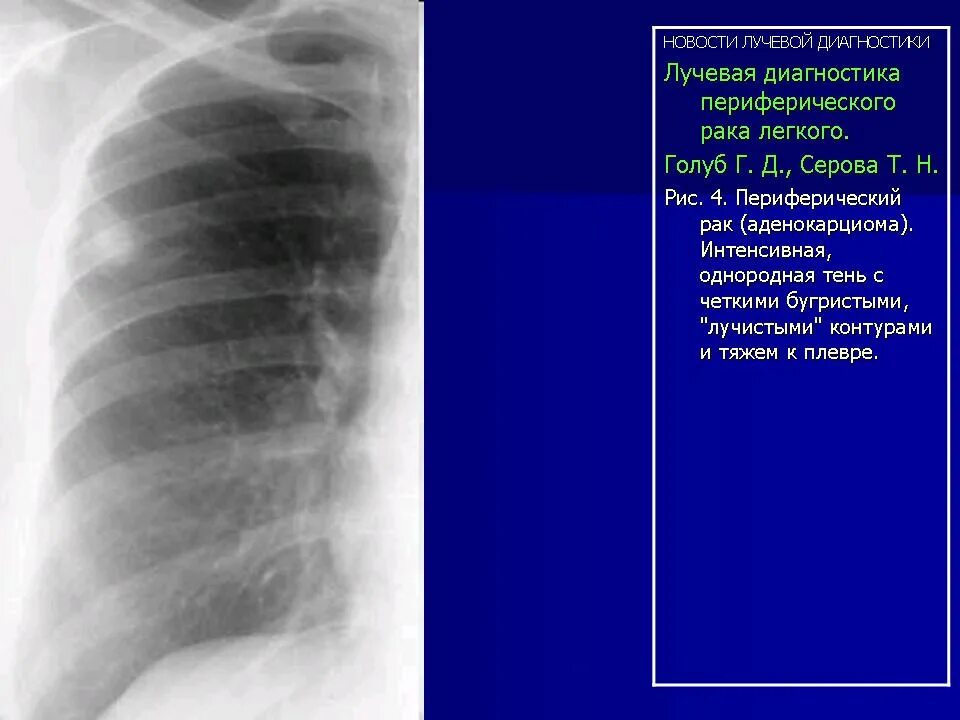

Лучевая при раке легких